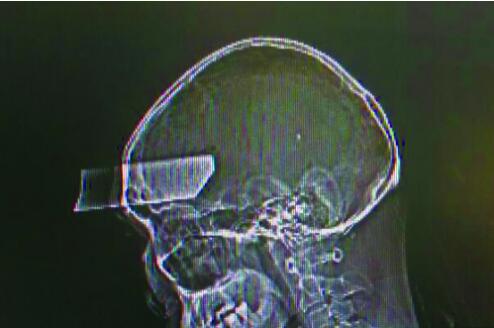

抵达医院神经外科时,距离事故发生已经40多分钟了。经头颅CT检查发现,一把长约12厘米的断刀片经右侧额骨插入右额叶,深约5厘米,相应额骨右侧及右眼眶顶壁碎裂骨折。

“患者比较幸运,刀从前额刺入,惊险地没有触及要害,如果刺入延髓生命中枢,可致患者直接死亡。”温江区人民医院神经外科主任甘全洲告诉家属,但是断刀是金属异物,患者颅内已有出血,而且刀片携带大量致病微生物,必须立即手术取出。随后,老马被送入手术室,医生顺利完整拔出了刀片。